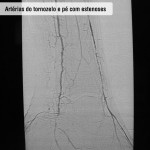

Placa de gordura que se calcifica na parede das artérias e diminui a nutrição de órgãos e membros devido à aterosclerose. Os fatores de risco para contrair a doença são: hereditariedade, diabetes, hipertensão arterial sistêmica, tabagismo, colesterol alto e sedentarismo. Pode se manifestar em três regiões: aorta ilíaca (mais comum em pessoas de 45 a 55 anos), femoro-poplíteo (frequente em pessoas de 55 a 65 anos) e infra-patelar (presente em pacientes diabéticos e acima de 65 anos).

Ao caminhar, o doente sente dor nas panturrilhas, coxas e nádegas (conhecida como claudicação intermitente). Nas obstruções mais extensas podem surgir úlceras nas pernas, nos pés ou dedos e até mesmo gangrena.

Doença obstrutiva em diabéticos